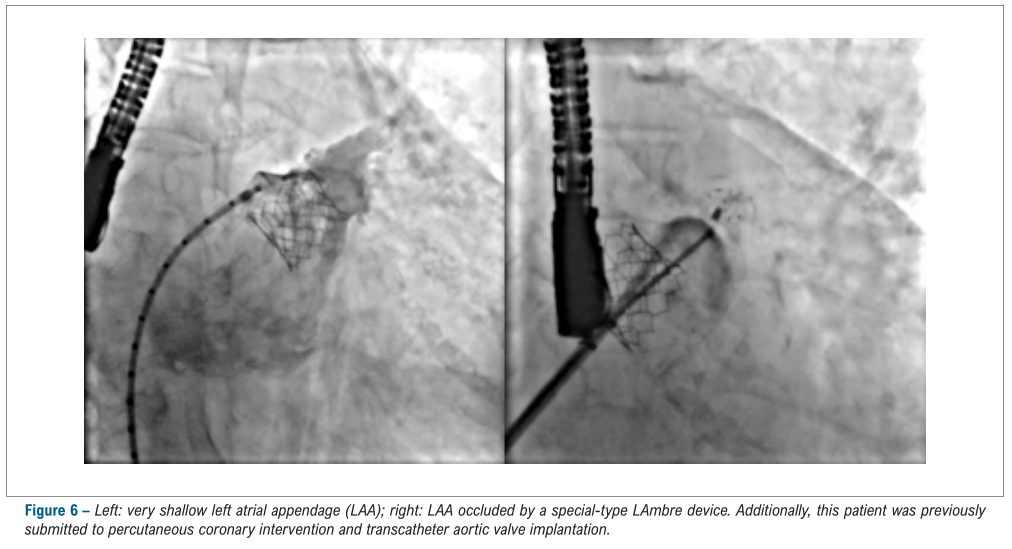

LAmbre™术中影像